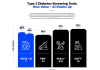

AI가 10초 음성으로 당뇨병 진단…”정확도 86% 이상”

스마트폰에 녹음된 10초 정도의 목소리만으로 제2형 당뇨병 여부를..